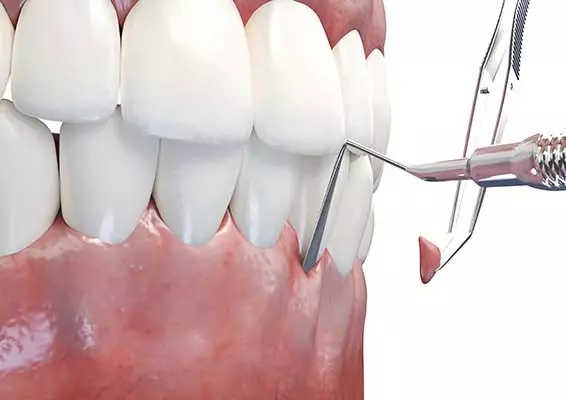

W tym wydaniu m.in: koferdam w adhezyjnych protokołach rekonstrukcyjnych, Low Dose – przełom w tomografii komputerowej CBCT, odpowiedzialność karna lekarza za błąd medyczny, wykorzystanie sonoabrazji w różnych dziedzinach stomatologii.